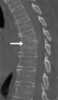

Osteomyelitis of spine

Osteomyelitis (OM) is an infection of bone. Symptoms may include pain in a specific bone with overlying redness, fever, and weakness. [Source: Wikipedia ]